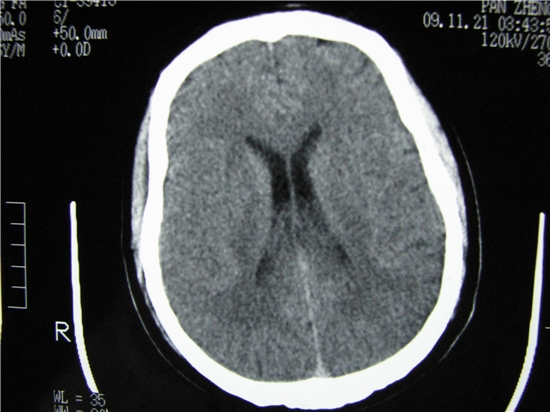

标题: CT23231:男 32岁 车祸伤,鼻腔内出血明显。 [打印本页]

标题: CT23231:男 32岁 车祸伤,鼻腔内出血明显。

额窦内及额部软组织内可见多发游离类骨质密度影,考虑额骨骨折可能。

左侧额骨、鼻骨骨折,头面部软组织肿胀。

左侧额骨、鼻骨骨折,额窦内的应该是游离骨块